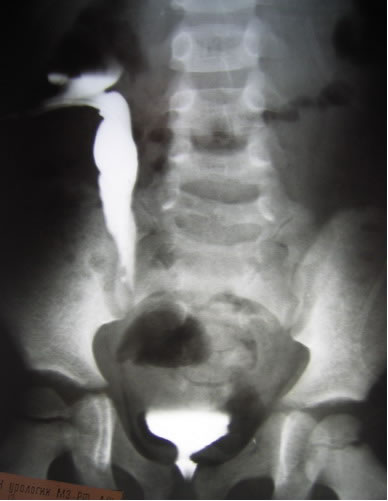

Цистография

Антеградная уретерография справа